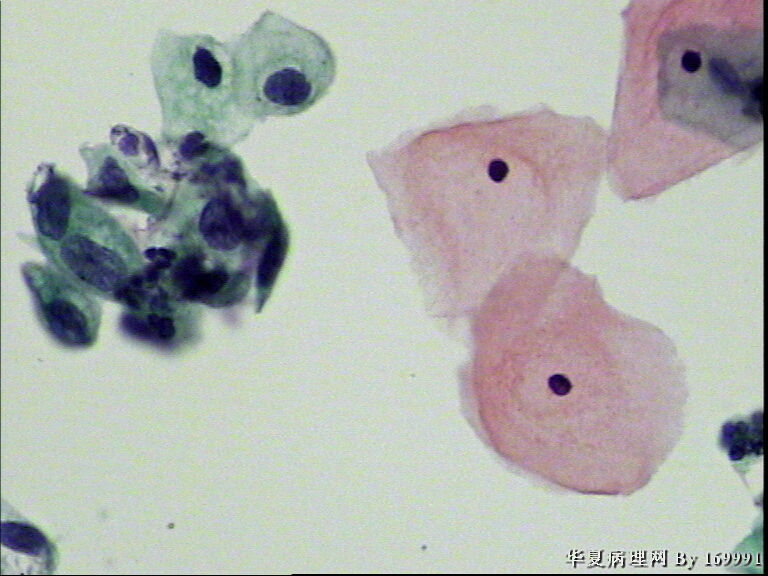

宫颈液基,患者,23岁,宫颈中糜

• 宫颈液基,患者,23岁,宫颈中糜图2

图2

我感觉报HSIL有点高了,就细胞的形态来看,核增大深染的基本上还是中层以及接近表层的细胞,结合患者年龄,我认为报LSIL更好一些。不知道对不对,请各位老师指教啦!

大家都看得不错。最高可能是CINII级,看活检了。

感觉像高级别,但患者年龄太小。ASC-H